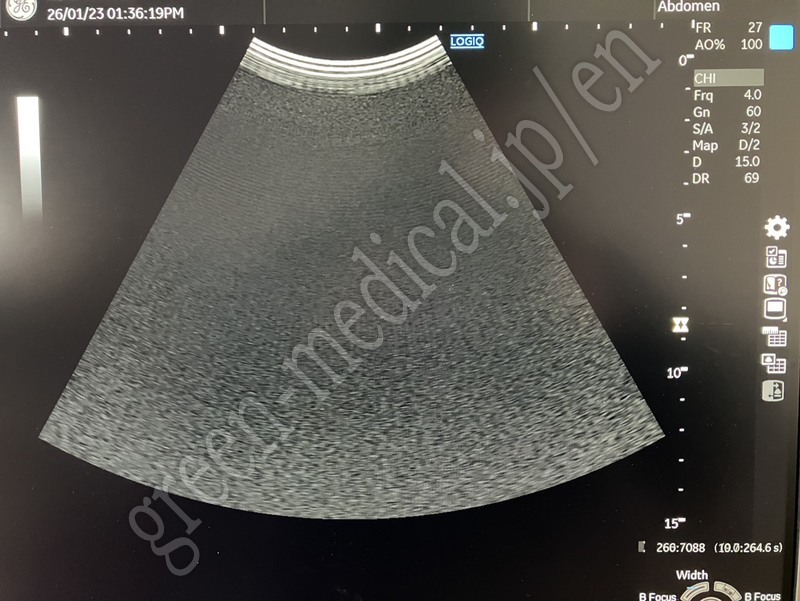

LOGIQ P10

2022 Logiq P10 R4.5

C1-5-RS Convex

L4-12t-RS Linear (Wideband linear array, with 4x configurable buttoms)

3Sc-RS Sector

BW printer

with CW Doppler, AFI, AutoIMT, TVI, DICOM, BFlow